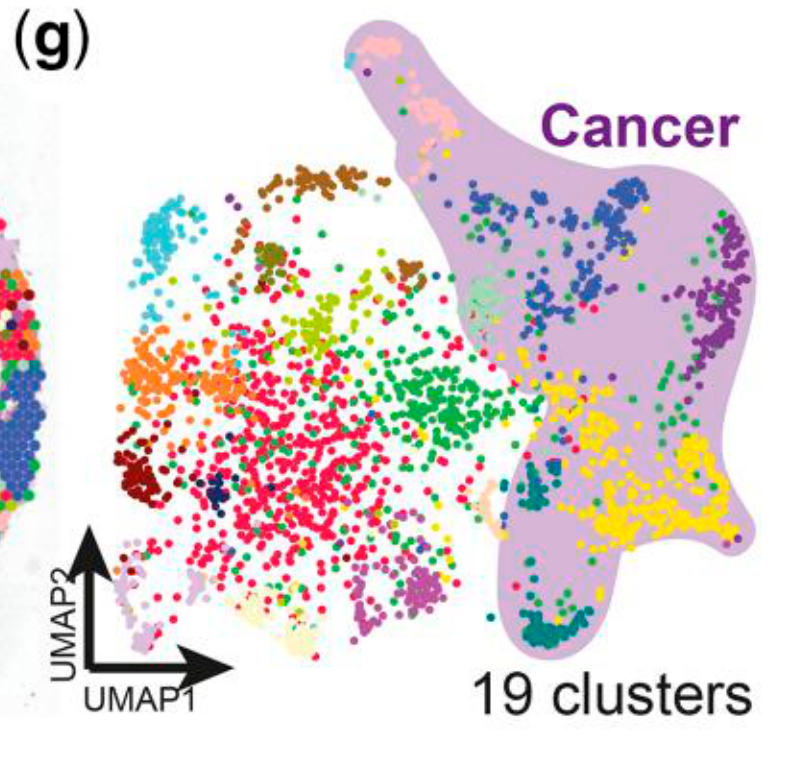

How are spatial domains distributed in embedding space with 2D analysis?